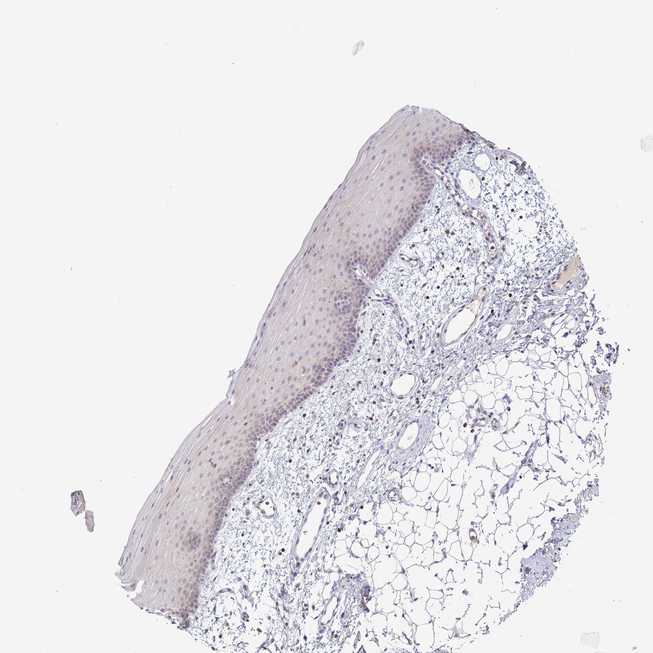

TISSUE PRIMARY DATA ORAL MUCOSA Show tissue menu

ORAL MUCOSA - Antibody stainingi

Antibody staining in the annotated cell types in the current human tissue is reported as not detected, low, medium, or high, based on conventional immunohistochemistry profiling in selected tissues. This score is based on the combination of the staining intensity and fraction of stained cells.

Each image is clickable and will lead to virtual microscopy that enables deeper exploration of all samples and also displays staining intensity scores, fraction scores and subcellular localization as well as patient and tissue information for each sample.

Antibody HPA042455Antibody HPA043579Antibody HPA049348Antibody CAB002491Antibody CAB016271

Squamous epithelial cells Not detectedMediumNot detectedNot detectedNot detected